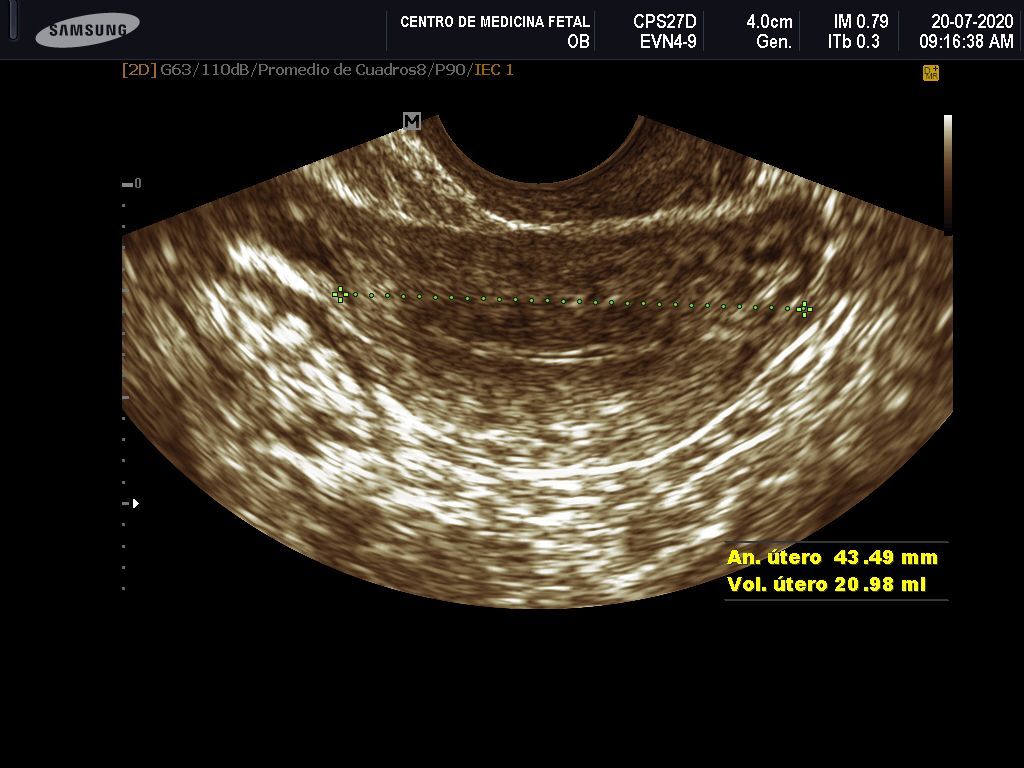

- Detección ecográfica transvaginal o pélvica y tratamiento de: Miomas, quistes de ovario, endometriosis, malformaciones uterinas